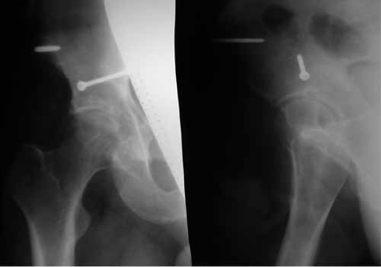

В случае, когда отломок локализуется выше ориентирной линии (рис. 1а, 1б) разрез производится до фасции большой ягодичной мышцы непосредственно по этой линии или несколько выше от проекции основания крестцово-подвздошного сочленения до верхушки большого вертела.

Обзорная рентгенограмма таза. Задне-верхний вывих бедра. Перелом верхнего отдела заднего края вертлужной впадины со смещением отломка.

Обзорная рентгенограмма таза. Вправленный вывих бедра. Перелом верхнего отдела заднего края вертлужной впадины со смещением отломка